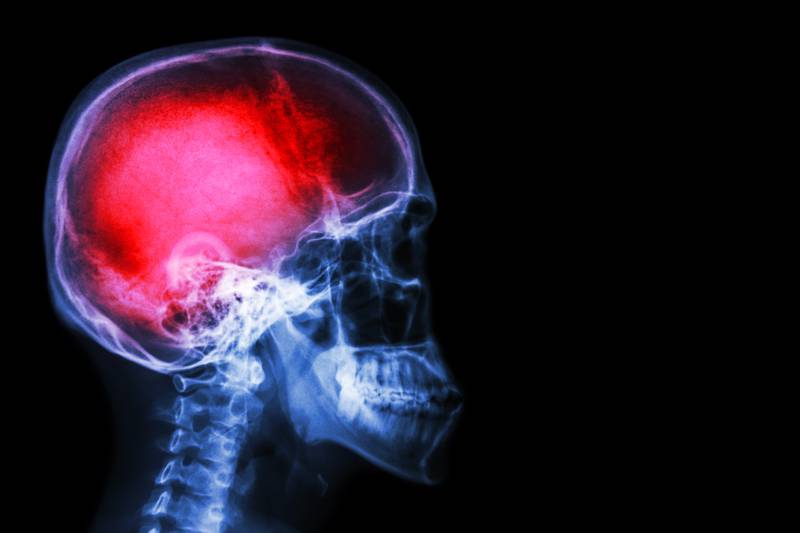

Veterans of the Global War on Terror who have suffered moderate-to-severe or penetrating traumatic brain injuries are at a significantly increased risk of developing brain cancer, according to a study published Thursday to the Journal of the American Medical Association’s open network.

Moderate or severe TBI showed a 90% increased risk for brain cancer, and those with penetrating TBI had a threefold risk, researchers from the Uniformed Services University of Health Sciences found.

The study examined the medical records of nearly 2 million veterans from 2004 to 2019, finding that while concussions ― also known as mild TBI― were not associated with an increased risk of brain cancer, more serious head injuries were.

Out of 2 million veterans, 0.02% of the group with no TBI or mild TBI developed brain cancer. Of those who endured moderate or severe TBI, 0.04% developed brain cancer. Brain cancer diagnoses were found in 0.06% of veterans who suffered an incident of penetrating TBI.